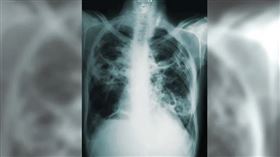

汪建民肺癌病逝! 醫嘆:轉移腦部撐不過

藝人汪建民在去年的7月時候,發現罹患了肺腺癌第四期,...

台比全球高2倍!肺癌4因子你有嗎?

肺癌已成國病之一,也是全球罹患人數最多的癌症。根據台...

2022/01/31 08:30